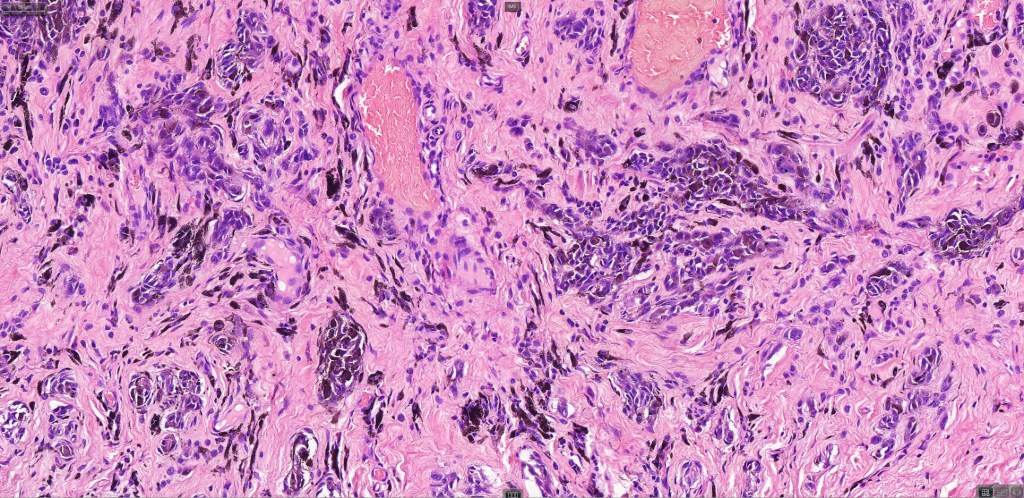

This is uncommon and presents clinically with a history of recent change in color of a common or less often congenital nevus causing concern for melanoma by the clinician. Some, but not all are probably deep penetrating and combined nevus variants. Others may represent follicular type-A cell nests. It is characterized by the presence of deep nest(s) of type -A nevus cells surrounded by & with overlying type-B nevus cells.